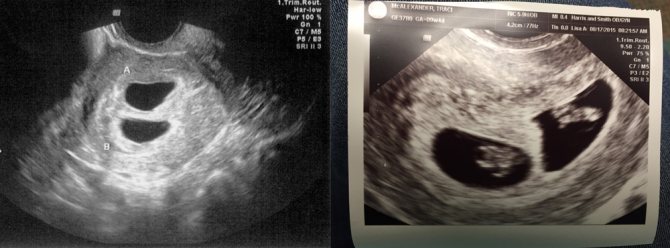

Как выглядит двойня на ранних сроках? Поначалу врач видит только два темных пятнышка. Кроме того, отчетливо прослушивается биение двух сердец, видны две плаценты и два амниотических пузыря. На фото можно увидеть снимок УЗИ близнецов.

На ранних сроках при проведении УЗИ оцениваются следующие параметры плода:

- копчико-теменной размер — КТР, близнецы обычно имеют меньшие размеры, чем одиночные эмбрионы, и к 12 неделе достигают роста 6 см и массы тела 8 г;

- бипариетальный размер — БПР, расстояние между височными костями черепа;

- частота сердечных сокращений — 110-150 уд/мин;

Нередко на снимке УЗИ заметно, что один эмбрион меньше другого. Если расхождение невелико и составляет всего лишь несколько миллиметров, то беспокоиться не нужно, размеры выровняются или в процессе беременности, или после рождения малышей.

Ультразвук

Наиболее надежный метод выявления многоплодной беременности – ультразвуковое обследование. Но его проведение на ранних сроках может показать только одного ребенка. В первом триместе вероятность выявления развития многоплодности достигает 29%, во втором и третьем -96%. Иногда происходят невероятные случаи обнаружения при родоразрешении третьего ребенка, не зафиксированного при скринингах.